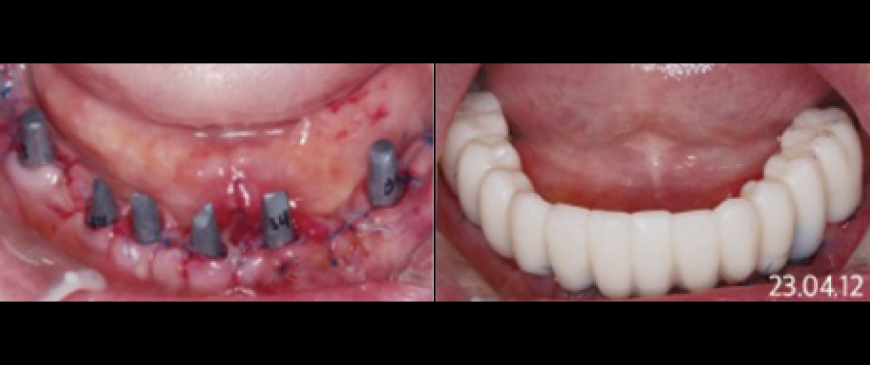

Fig 10

Four days after the surgery, custom abutments and a PMMA bridge were placed.

Fig 12

The final prosthesis was placed approximately 3 months later, after the soft tissue stabilized.